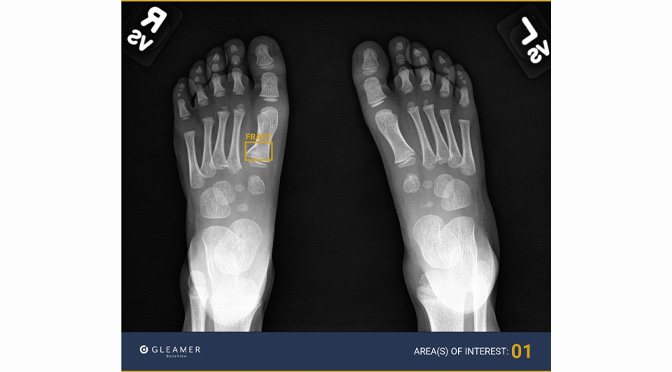

Photo caption: Gleamer BoneView AI identifies bone abnormalities, placing a yellow box around areas of concern in an image.

Trained on a massive database of X-ray images and powered by deep learning algorithms, Gleamer BoneView AI identifies bone abnormalities, placing a yellow box around areas of concern in an image. It is especially adept at identifying subtle signs of mild bone breaks such as buckle fractures.